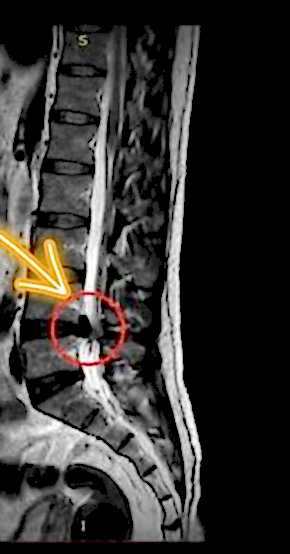

Bel ve boyun fıtığı, omurgadaki disklerin yerinden kayması veya dışarı çıkması sonucu oluşan bir durumdur. Bu diskler, omurlar arasındaki yastıkçıklar olarak görev yapar ve omurga hareketlerini rahatlatır. Ancak, bu disklerin kayması veya patlaması, sinirlere baskı yaparak ağrıya, uyuşma ve kuvvet kaybına neden olabilir.

Bel fıtığı genellikle bel bölgesindeki omurlar arasında meydana gelirken, boyun fıtığı ise boyun omurları arasında oluşur. Bu rahatsızlıkların belirtileri arasında sırt, bel ve boyun ağrıları, bacaklarda uyuşma, kollarda güçsüzlük gibi şikayetler yer alır. Eğer patlamış fıtık tedavisi arıyorsanız, Gaziantep bel fıtığı tedavisi ve boyun fıtığı tedavisi için doğru adrestesiniz.